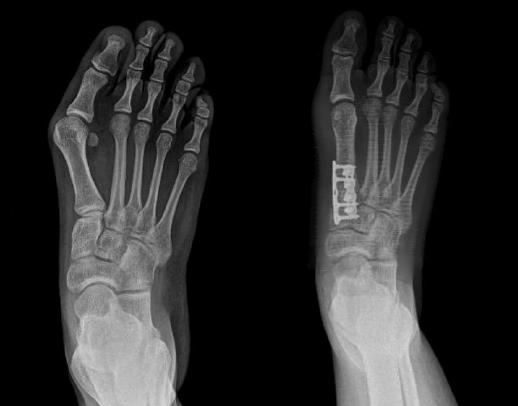

Hueter en 1870 fue el primero en introducir el término hallux valgus y, a pesar de que han pasado 150 años, aún existen muchos interrogantes acerca de esta deformidad tan frecuente en ortopedia.

En la actualidad, el paradigma de la tridimensionalidad de la deformidad promulgado por Dayton et al. nos acerca a comprender muchos de esos interrogantes, aunque quedan muchos por resolver.

Creemos que la primera articulación tarsometatarsiana (1.ª ATMT) desempeña un papel importante en la génesis de la deformidad y es el lugar indicado para la corrección del hallux valgus cuando esté presente una rotación del primer metatarsiano (M1).